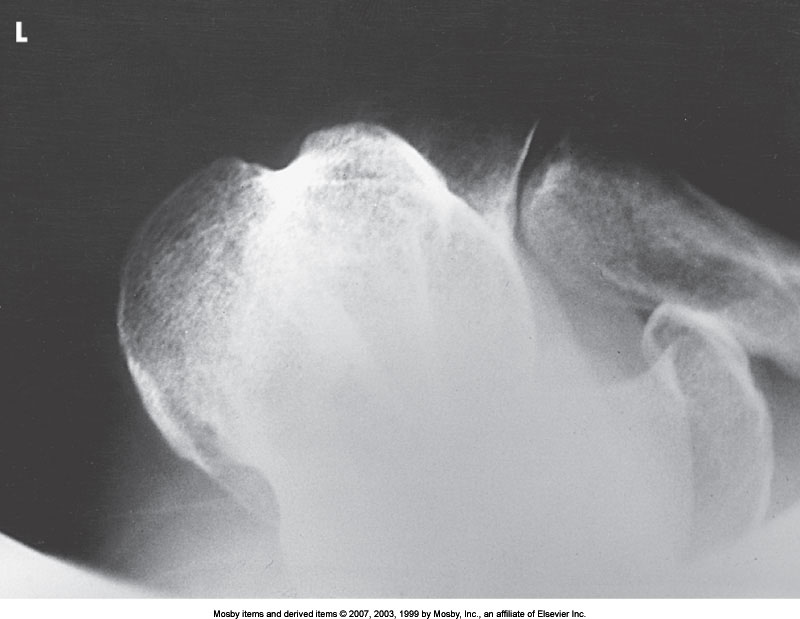

What position is demonstrated?

Tangential Shoulder (Intertubercular/Bicipital Groove)